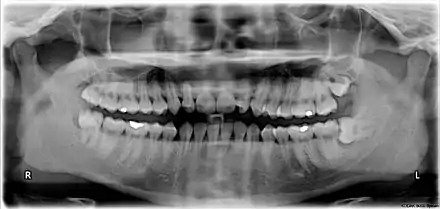

ISO notation upper jaw

ISO notation lower jaw